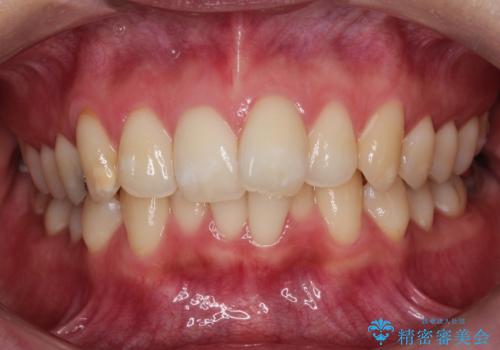

驚くほど短期間で前歯のガタツキを解消! マウスピース矯正の効果

- 前歯のでこぼこが気になると来院されました。

マウスピース矯正治療を選択しました。

奥歯の噛み合わせは綺麗に噛んでいたため、前歯の叢生(でこぼこ)を、短期間で治療完了するように計画しました。

奥歯の噛み合わせは整っていたため、前歯の並びを美しく修正することに専念できました。マウスピース矯正による治療で短期間で改善しました。